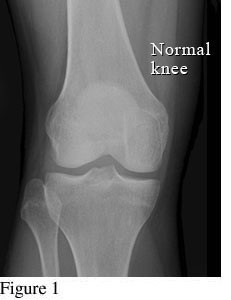

Hình ảnh so sánh giữa khớp bình thường và khớp bị thoái hóa khớp gối

Để phân biệt các giai đoạn của bệnh thoái hóa khớp gối, cần dựa vào phim X- quang theo tiêu chuẩn chẩn đoán thoái hoá khớp của Kellgren và Lawrence như sau: